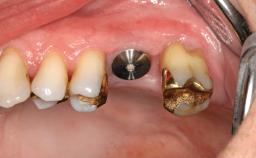

Surgical treatment of a 68-year-old female patient who experienced failure of her conventional bridge in the right maxilla. After removal of the compromised abutment teeth and a healing period of 6 weeks, a sinus floor elevation procedure using the lateral window technique and a composite graft to correct the insufficient bone height is carried out.

Two dental implants are placed in the same surgical session. The case concludes with the presentation of the final fixed dental prosthesis with a distal cantilever unit.